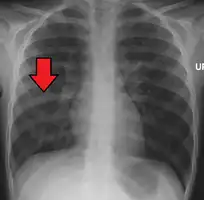

| Chest X-ray of a pneumonia caused by influenza and Haemophilus influenzae, with patchy consolidations, mainly in the right upper lobe (arrow) | |

X-ray presentations of pneumonia may be classified as lobar pneumonia, bronchopneumonia, lobular pneumonia, and interstitial pneumonia.[66] Bacterial, community-acquired pneumonia classically show lung consolidation of one lung segmental lobe, which is known as lobar pneumonia.[34] However, findings may vary, and other patterns are common in other types of pneumonia.[34] Aspiration pneumonia may present with bilateral opacities primarily in the bases of the lungs and on the right side.[34] Radiographs of viral pneumonia may appear normal, appear hyper-inflated, have bilateral patchy areas, or present similar to bacterial pneumonia with lobar consolidation.[34] Radiologic findings may not be present in the early stages of the disease, especially in the presence of dehydration, or may be difficult to interpret in the obese or those with a history of lung disease.[21] Complications such as pleural effusion may also be found on chest radiographs. Laterolateral chest radiograph can increase the diagnostic accuracy of lung consolidation and pleural effusion.[33]